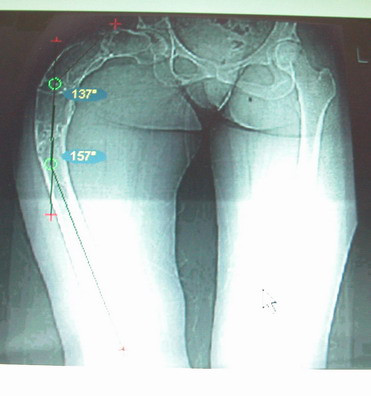

Возможна аппаратная коррекция оси с формированием клиновидного регенерата, которая решила бы и проблему укорочения (что, впрочем, нужно уточнить по схеме, сделанной по рентгенограмме с хорошим захватом смежных суставов - схемка по присланному снимку в приложении). По окончании коррекции - блокируемый стержень, который и сократит время пребывания в аппарате, и вообще возврата к нормальной жизни, а также будет мерой профилактики патологических переломов.

Собственно сустав не беспокоит, объем движений полный. По скиаграммам получается, что достаточно одной остеотомии на вершине деформации, чтобы восстановить длину и вывести коленный сустав в нужное положение.

Моё мнение, что двойная остеотомия бедра с аппаратом Илизарова + Гексаподный механизм, или Тэйлора, В данной ситуации является методом выбора. Я очень извеняюсь за качество прилагаемых снимков, в которых я постарался отразить разницу междe одной и двумя остеотомиями бедра.

jo> отразить разницу межде одной и двумя остеотомиями бедра.

Скорее всего, второй уровень может оказаться нелишним лишь при переходе с аппарата на интрамедуллярный стержень. И его не поздно будет пересечь именно в момент введения гвоздя, если будет угроза перфорации стенки канала.